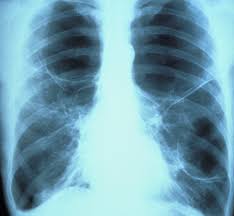

Health Effects Of Secondhand Smoke Cdc from www.cdc.gov Lung cancer occurrence in never smokers. Age, secondhand smoke, cooking fumes, radon, environmental exposures, genetic factors, underlying lung disease, oncogenic viruses, and estrogens. Sidestream smoke (the more toxic of the two) is. Workplace exposures to asbestos, diesel exhaust or certain other chemicals can also cause lung cancers in some people who don't smoke. Lung cancer is a type of cancer that starts in the lungs, causing cells to divide in the lungs uncontrollably. Due to their location away from the large airways, these tumors often grow quite large or spread before they cause any symptoms. There are two different types. Lung cancer can be caused by many risk factors other than smoking cigarettes.

Cigarette smoking is the number one risk factor for lung cancer. In the past five to 10 years, new knowledge about lung cancer has changed the way it is treated in both smokers and nonsmokers. Lung adenocarcinomas tend to grow in the outer regions of the lungs. Adenocarcinoma starts in the mucus cells that line your lungs. Lung cancer is a type of cancer that starts in the lungs, causing cells to divide in the lungs uncontrollably.